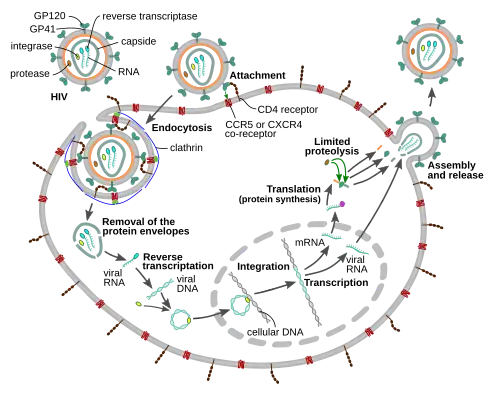

Replication cycle

Entry to the cell

The HIV virion enters macrophages and CD4+ T cells by the adsorption of glycoproteins on its surface to receptors on the target cell followed by fusion of the viral envelope with the target cell membrane and the release of the HIV capsid into the cell.[59][60]

Entry to the cell begins through interaction of the trimeric envelope complex (gp160 spike) on the HIV viral envelope and both CD4 and a chemokine co-receptor (generally either CCR5 or CXCR4, but others are known to interact) on the target cell surface.[59][60] Gp120 binds to integrin α4β7 activating LFA-1, the central integrin involved in the establishment of virological synapses, which facilitate efficient cell-to-cell spreading of HIV-1.[61] The gp160 spike contains binding domains for both CD4 and chemokine receptors.[59][60]

The first step in fusion involves the high-affinity attachment of the CD4 binding domains of gp120 to CD4. Once gp120 is bound with the CD4 protein, the envelope complex undergoes a structural change, exposing the chemokine receptor binding domains of gp120 and allowing them to interact with the target chemokine receptor.[59][60] This allows for a more stable two-pronged attachment, which allows the N-terminal fusion peptide gp41 to penetrate the cell membrane.[59][60] Repeat sequences in gp41, HR1, and HR2 then interact, causing the collapse of the extracellular portion of gp41 into a hairpin shape. This loop structure brings the virus and cell membranes close together, allowing fusion of the membranes and subsequent entry of the viral capsid.[59][60]

After HIV has bound to the target cell, the HIV RNA and various enzymes, including reverse transcriptase, integrase, ribonuclease, and protease, are injected into the cell.[59] During the microtubule-based transport to the nucleus, the viral single-strand RNA genome is transcribed into double-strand DNA, which is then integrated into a host chromosome.

HIV can infect dendritic cells (DCs) by this CD4-CCR5 route, but another route using mannose-specific C-type lectin receptors such as DC-SIGN can also be used.[62] DCs are one of the first cells encountered by the virus during sexual transmission. They are currently thought to play an important role by transmitting HIV to T cells when the virus is captured in the mucosa by DCs.[62] The presence of FEZ-1, which occurs naturally in neurons, is believed to prevent the infection of cells by HIV.[63]

HIV-1 entry, as well as entry of many other retroviruses, has long been believed to occur exclusively at the plasma membrane. More recently, however, productive infection by pH-independent, clathrin-mediated endocytosis of HIV-1 has also been reported and was recently suggested to constitute the only route of productive entry.[64][65][66][67][68]

Replication and transcription

Shortly after the viral capsid enters the cell, an enzyme called reverse transcriptase liberates the positive-sense single-stranded RNA genome from the attached viral proteins and copies it into a complementary DNA (cDNA) molecule.[69] The process of reverse transcription is extremely error-prone, and the resulting mutations may cause drug resistance or allow the virus to evade the body's immune system. The reverse transcriptase also has ribonuclease activity that degrades the viral RNA during the synthesis of cDNA, as well as DNA-dependent DNA polymerase activity that creates a sense DNA from the antisense cDNA.[70] Together, the cDNA and its complement form a double-stranded viral DNA that is then transported into the cell nucleus. The integration of the viral DNA into the host cell's genome is carried out by another viral enzyme called integrase.[69]

The integrated viral DNA may then lie dormant, in the latent stage of HIV infection.[69] To actively produce the virus, certain cellular transcription factors need to be present, the most important of which is NF-κB (nuclear factor kappa B), which is upregulated when T cells become activated.[71] This means that those cells most likely to be targeted, entered and subsequently killed by HIV are those actively fighting infection.

Assembly and release

The final step of the viral cycle, assembly of new HIV-1 virions, begins at the plasma membrane of the host cell. The Env polyprotein (gp160) goes through the endoplasmic reticulum and is transported to the Golgi apparatus where it is cleaved by furin resulting in the two HIV envelope glycoproteins, gp41 and gp120.[88] These are transported to the plasma membrane of the host cell where gp41 anchors gp120 to the membrane of the infected cell. The Gag (p55) and Gag-Pol (p160) polyproteins also associate with the inner surface of the plasma membrane along with the HIV genomic RNA as the forming virion begins to bud from the host cell. The budded virion is still immature as the gag polyproteins still need to be cleaved into the actual matrix, capsid and nucleocapsid proteins. This cleavage is mediated by the packaged viral protease and can be inhibited by antiretroviral drugs of the protease inhibitor class. The various structural components then assemble to produce a mature HIV virion.[89] Only mature virions are then able to infect another cell.